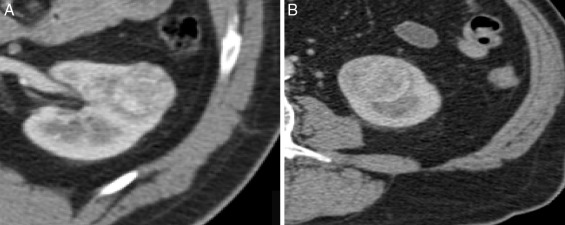

Em termos de densidade e captação de contraste também não identificámos diferenças com significado estatístico (fig. 3 ). A densidade e captação de contraste dos oncocitomas e CCR‐cc são aproximadamente idênticas, resultados que vão ao encontro de outros estudos anteriormente realizados15 .

À esquerda, temos um oncocitoma. À direita, um CCR‐cc. Não existem diferenças ...

Figura 3.

À esquerda, temos um oncocitoma. À direita, um CCR‐cc. Não existem diferenças morfológicas distintivas, bem como a captação de contraste foi aproximadamente idêntica: 49 HU e 51 HU, respetivamente.